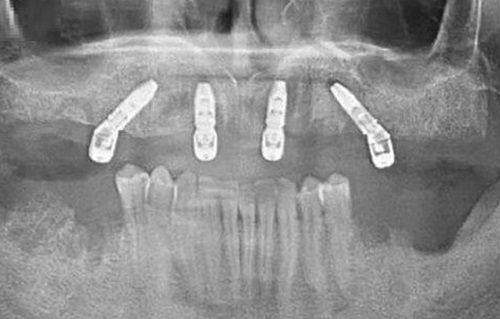

他还擅长高难度种植All - on - 4。这种种植技术对于医生的技术要求特别高,张晖医生凭借自己的不错技艺,已经成功为多位患者实施了该手术。他会在手术前与患者进行充分的沟通,让患者了解手术的过程和预期成效,缓解患者的紧张情绪。在手术中,他操作熟练,每一个步骤都严谨细致,确保手术的顺利进行。

在全口种植和半口种植方面,他有着丰富的经验。全口或半口牙缺失会重度影响患者的生活质量,张晖医生会为患者制定详细的种植方案。他会考虑患者的面部美观、咀嚼功能等因素,选择合适的种植体和修复方式。在种植过程中,他会与团队密切配合,确保手术的顺利进行。手术后,他会对患者进行定期的回访和检查,指导患者进行口腔护理,让患者能够尽快适应新的牙齿。